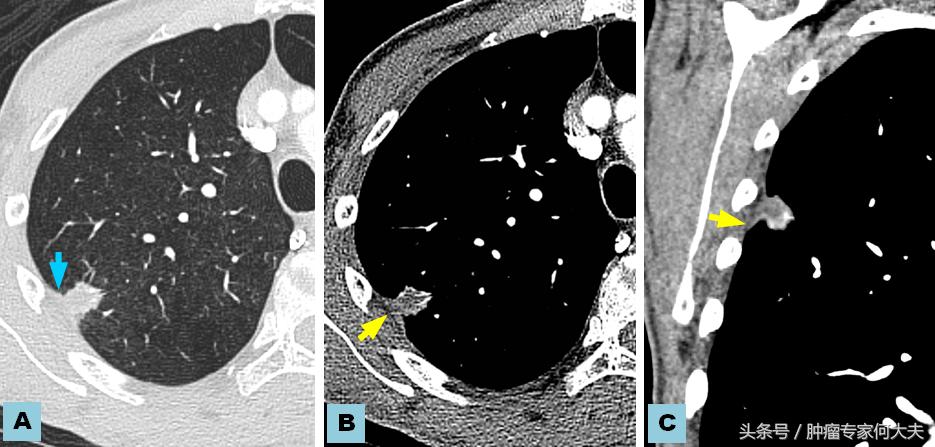

肺影像学

在第二年接近第三年的那次复查中,小豆被医生告知右肺也长了瘤子,医生建议小豆穿刺活检,小豆还是比较配合的,做了肺穿刺活检术,术后病理结果证实也是肺腺癌,和以前病理结果一样,医生推测可能是转移,并对取下的组织进行了基因检测,仍然没有检测到敏感突变基因,但医生建议小豆可以尝试口服“易瑞沙”,因为在生病的2年多时间里,小豆研读了很多肺癌的专业书籍,对肺癌的知识了解甚多,因此她同意了口服靶向药,在口服靶向药的两个月里,除过面部皮疹,没有其他不良反应,但用药三个月后,复查肺部CT,病灶依然没有明显变小迹象。医生考虑无效,于是就把靶向药停了。没有任何治疗,她还能撑多久?她自己不知道,医生们也众说纷纭,反正总体是时间不会太久,有的医生说也就半年一年左右,小豆说当时自己想“反正都这样了,与天争命也无济于事,静静等待未来会发生什么”。

就这样,读书、看报、上网,有时候和朋友出去游游逛逛,虽然癌症在身,她不能积极作为,只能听天由命,但是半年过去了,右肺出现的病灶生长势头不明显,一年过去了,两年过去了,三年过去了,一直在复查,但是复查的结果总是说变化不显著。但医生仔细对比三年之初与三年之末(最近)的片子,瘤子是有所长大,但都长的不算多,个别小病灶甚至自然变小。 最近,小豆说自己喘的明显了,夜里咳嗽厉害,难以成眠,要来查查,我给做了胸部CT检查,结果提示两肺多发占位病变,对比了她3年前刚发现右肺时的片子,这次明显变大,目前尚未做出诊疗计划。但针对小豆这样的病人,实属少见。人类针对肿瘤的认识仍然处于很原始的阶段。就拿肺癌来说,现代医学研究算是比较成功的一种瘤种,已经认识到一部分肺癌患者因为存在某些基因突变可以从治疗中获益,但是没有突变的患者并不是一定就很危险,个体差异相当大。希望每个人不要因为得了肿瘤,就自暴自弃。